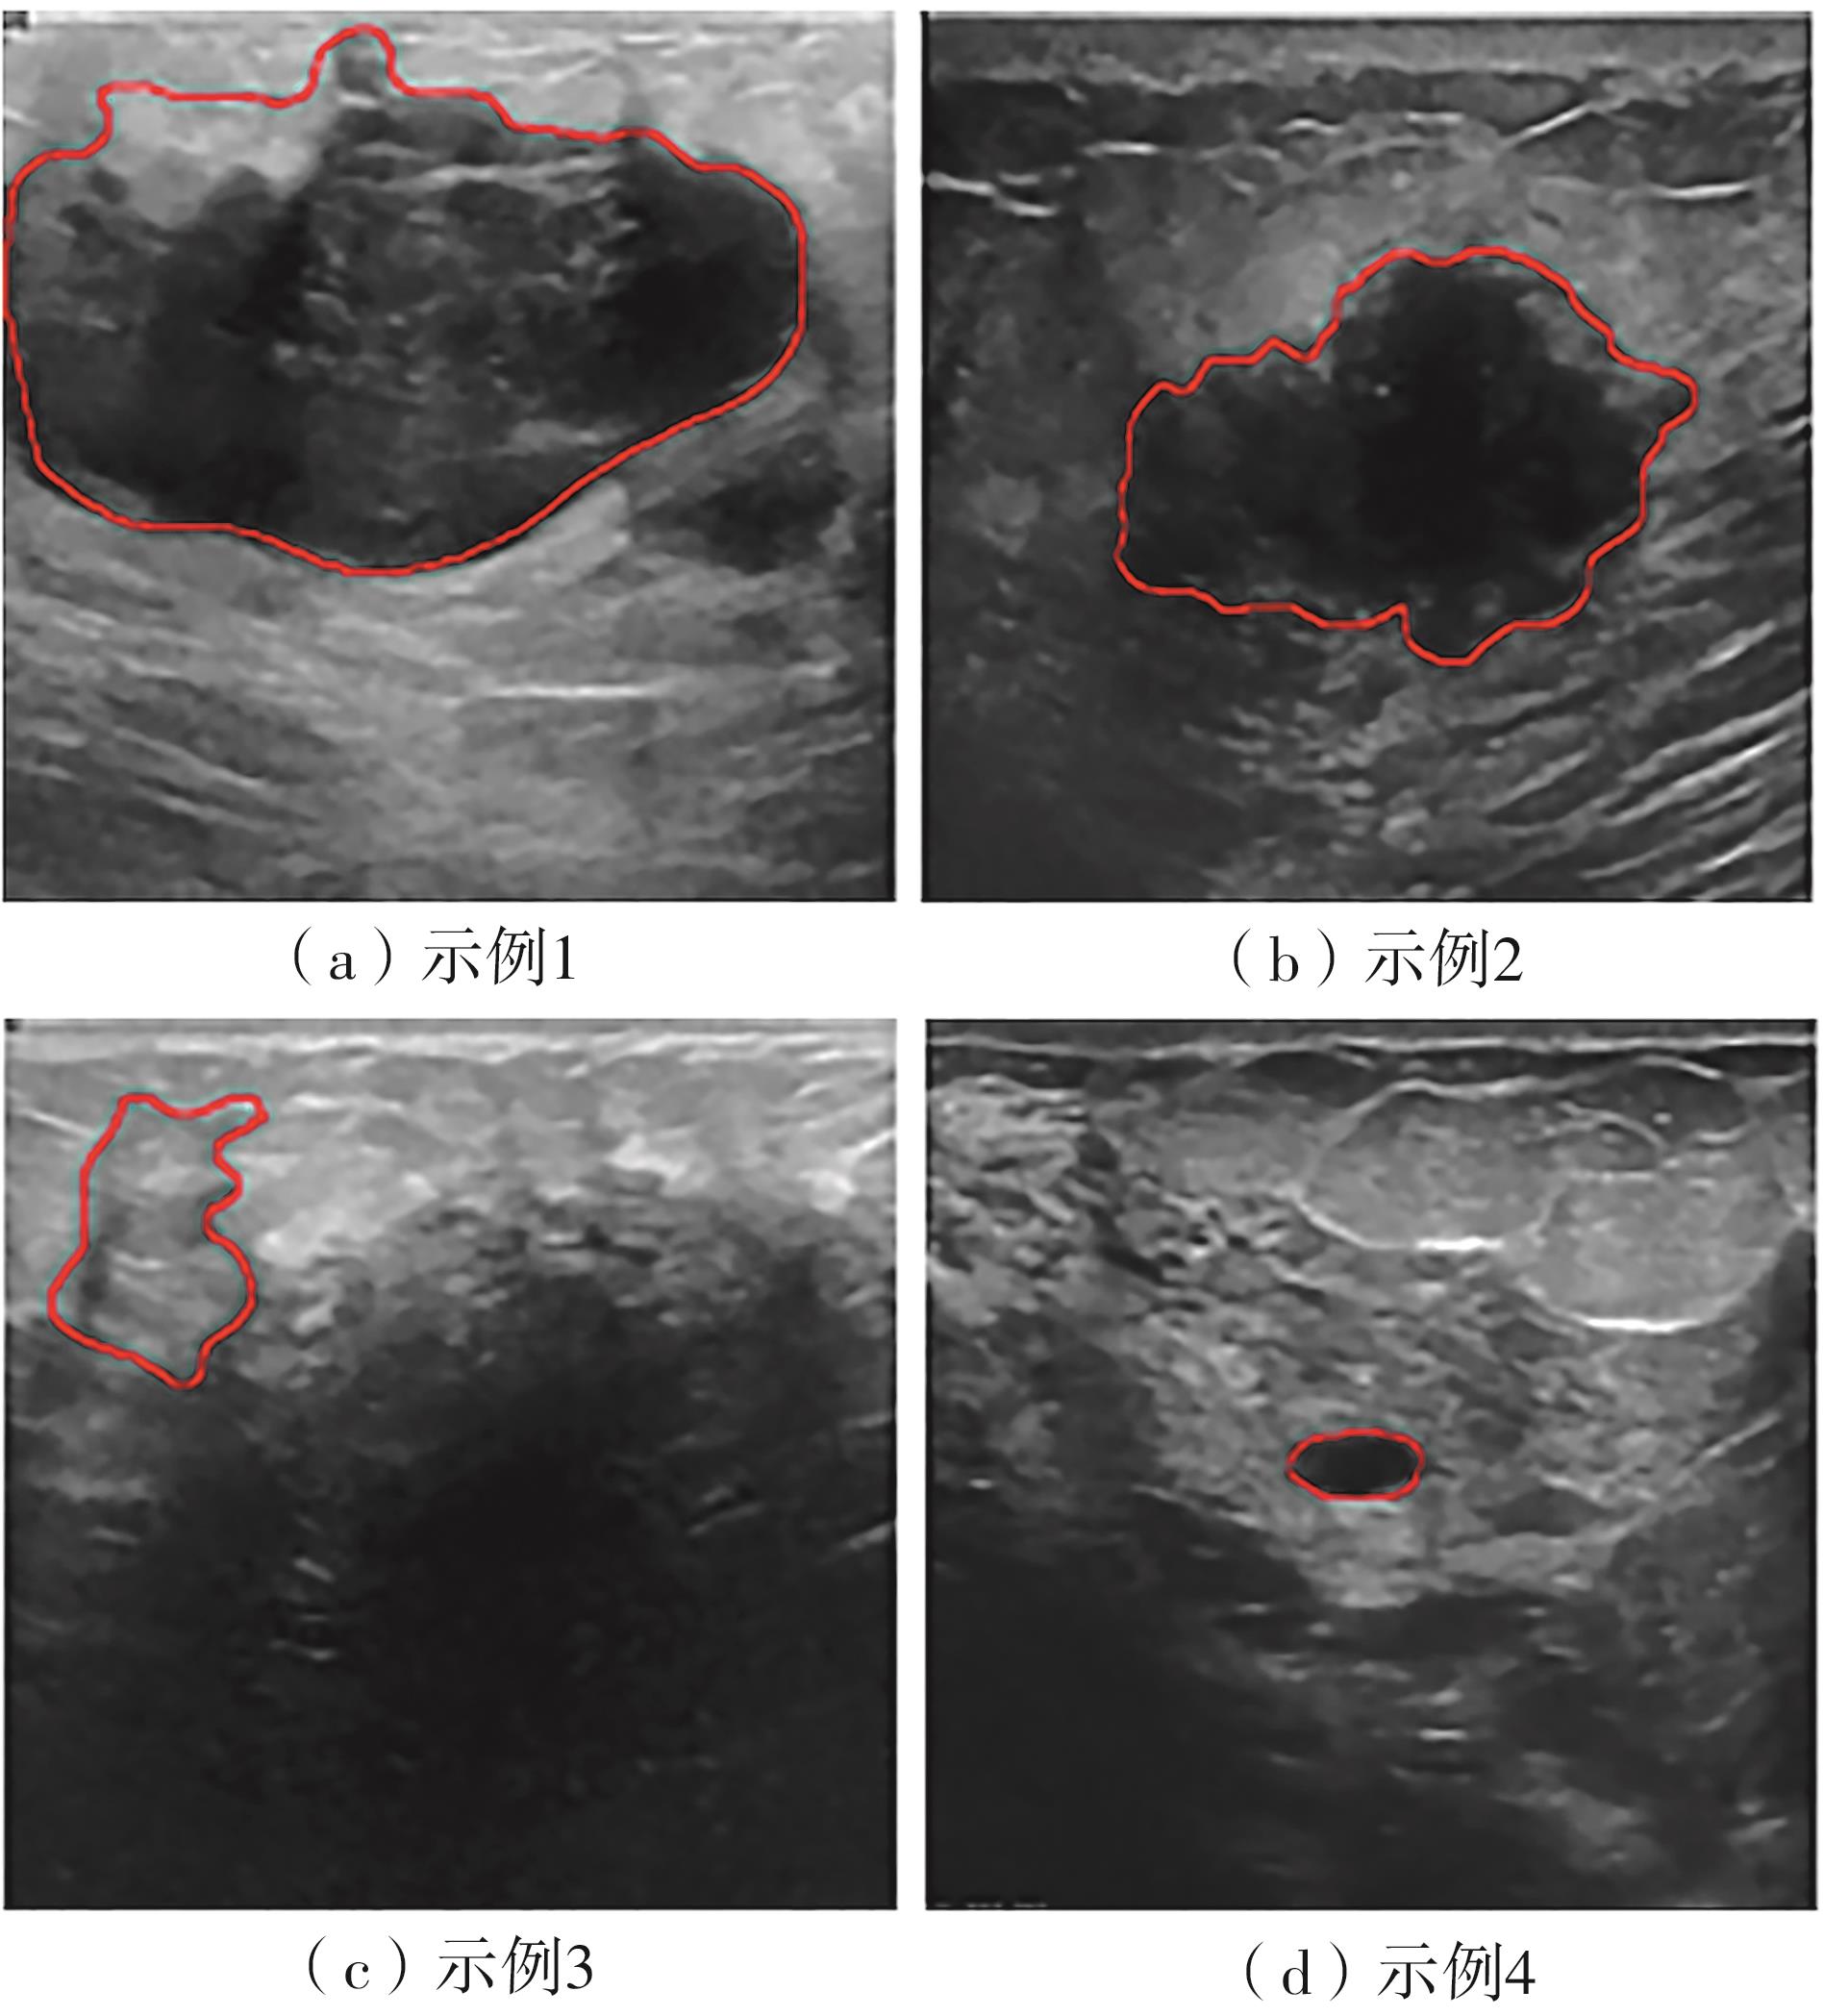

乳腺癌是全球女性最常见的恶性肿瘤之一,准确的病变分割对于乳腺癌的早期诊断与治疗具有重要意义。然而,由于病变形态的多样性以及超声成像机制的复杂性,现有基于深度学习的乳腺超声图像病变分割方法在分割准确性方面仍面临巨大挑战。为进一步提升乳腺超声图像中病变区域的分割精度,该文基于经典U-Net架构,提出了一种新型乳腺超声图像病变分割网络(CWSASKM-BBAM-Net)。首先,在网络中引入逐通道空间自适应选择核卷积模块(CWSASKM),根据不同通道的语义特征为每个空间位置自适应选择感受野大小,以增强多尺度信息的建模能力;然后,引入双向边界感知机制(BBAM),通过融合正向与反向注意力,对目标显著区域及其边界进行协同建模,同时逐步提升对非显著区域与病变区域的区分能力,以进一步强化边界信息的表达;最后,在3组公开乳腺超声图像数据集(BUSI、UDIAT和STU)上开展分割实验。结果表明:该方法在数据集BUSI上的杰卡德指数、精确率、召回率和Dice相似系数分别为71.97%、82.85%、81.40%和80.44%,较次优方法分别提升1.69、1.05、1.28和1.84个百分点;在数据集UDIAT上,这4项指标分别达到78.14%、88.31%、86.73%和86.10%,较次优方法分别提升了2.75、2.04、0.56和2.01个百分点;在外部数据集STU上,该方法也取得了优于其他方法的整体表现。实验结果表明,CWSASKM-BBAM-Net在乳腺超声图像分割任务中展现出更优的整体性能。